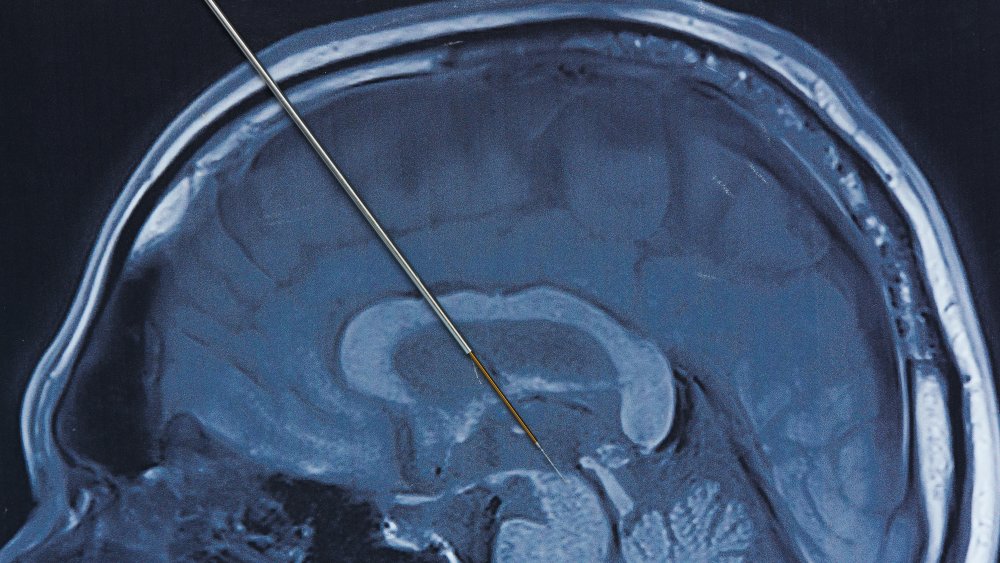

La technique utilisée est la stimulation cérébrale profonde (deep brain stimulation, DBS) : on perce deux trous dans le crâne — décrits comme « de la taille d’une pièce » — puis on implante deux électrodes dans des zones ciblées du cerveau. Ces électrodes délivrent des impulsions électriques censées moduler les circuits neuronaux impliqués dans le comportement addictif.